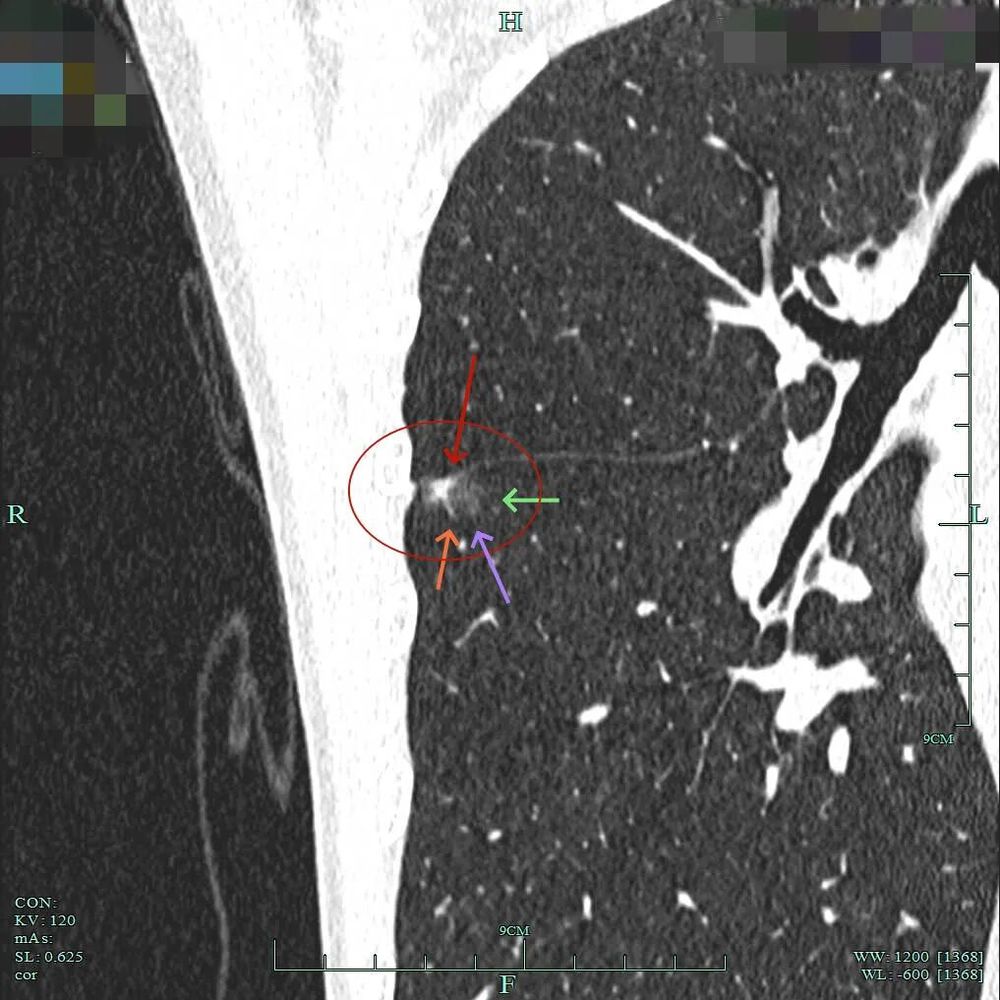

小血管进入以及灶内小部分密度偏高,与叶间裂没有间隙,是紧贴的。

灶内密度不均,叶间裂处增厚与密度增高,血管进入,表面不平以及细毛刺可见。

病灶混合密度,实性成分有收缩力与纠集感,磨玻璃部分密度较低,表面不平,细毛刺可见,紧贴叶间裂。